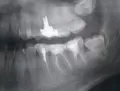

У меня заболели нижние зубы, потом начало отдавать в верхние. Сходила к дежурному врачу на приём. Он определил, что боль идет от восьмерки снизу, положил лекарство, сказал, если будет болеть, необходимо идти удалять. Сходила удалила, т.к. болело пол челюсти.

Хотела спросить, боль в верхних зубах должна сразу пройти или постепенно? Или мне снова идти к врачу, если будет ноющая боль в верхних зубах?